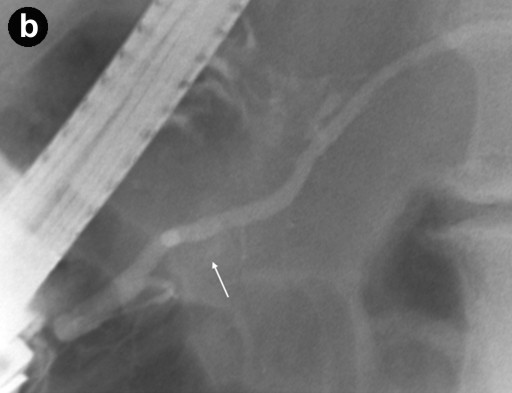

A 79-year-old asymptomatic women was found to have a serum CA 19-9 of 210 U/mL (reference range: 0-37 U/mL) during a general medical examination in 2000; the CEA level was 1.8 ng/mL (reference range: 0-5.0 ng/mL). They were done by her primary care physician because of a family history of breast and ovarian cancers. Computer tomography (CT) and magnetic resonance imaging cholangiopancreatography (MRCP) examinations in 2000, 2001, and 2002 from an outside facility reported stable small cysts at the head of the pancreas. The patient had never smoked or been an alcohol drinker. She had no history of pancreatitis or abdominal trauma. Her past medical history was significant for recurrent pneumonia, partial hysterectomy, and gastroesophageal reflux disease. Upon referral to our institution in 2003, MRCP demonstrated several subcentimeter pancreatic cysts in communication with a non-dilated pancreatic duct; endoscopic cholangiopancreatography (ERCP) revealed a subcentimeter cyst in the pancreatic head, communicating with the main pancreatic duct (Figure 1). No pancreatic abnormalities were seen on endoscopic ultrasound (EUS). High resolution CT of the chest showed bronchiectasis predominately in the right middle lobe and lingula consistent with Lady Windermere syndrome (Figure 2). In 2005, the patient was hospitalized several times with the diagnosis of "community acquired pneumonia." Repeat high resolution CT of the chest showed worsening of bronchiectasis with Mycobacterium avium-intracellulare complex-positive sputum cultures. The Mycobacterium avium-intracellulare complex infection was not treated because the positive cultures were thought to be due to colonization. In 2006, the patient was hospitalized again for pneumonia and triple therapy (rifampin, ethambutol, azithromycin) was started for Lady Windermere syndrome. Due to side effects, the therapy was discontinued after 3 months of treatment.

Figure 2. Lady Windermere syndrome. Axial CT image (a.) shows bronchiectasis (white arrows) in the right middle lobe (RML) and lingula with clustered small nodules (yellow arrows) representing bronchioles filled with mucus, fluid, or pus ("tree-in-bud" appearance). In addition, coronal CT image (b.) shows "tree-in-bud" appearance involving both upper lobes as well as the lower lungs (yellow arrows); this is consistent with Mycobacterium avium-intracellulare complex infection. |